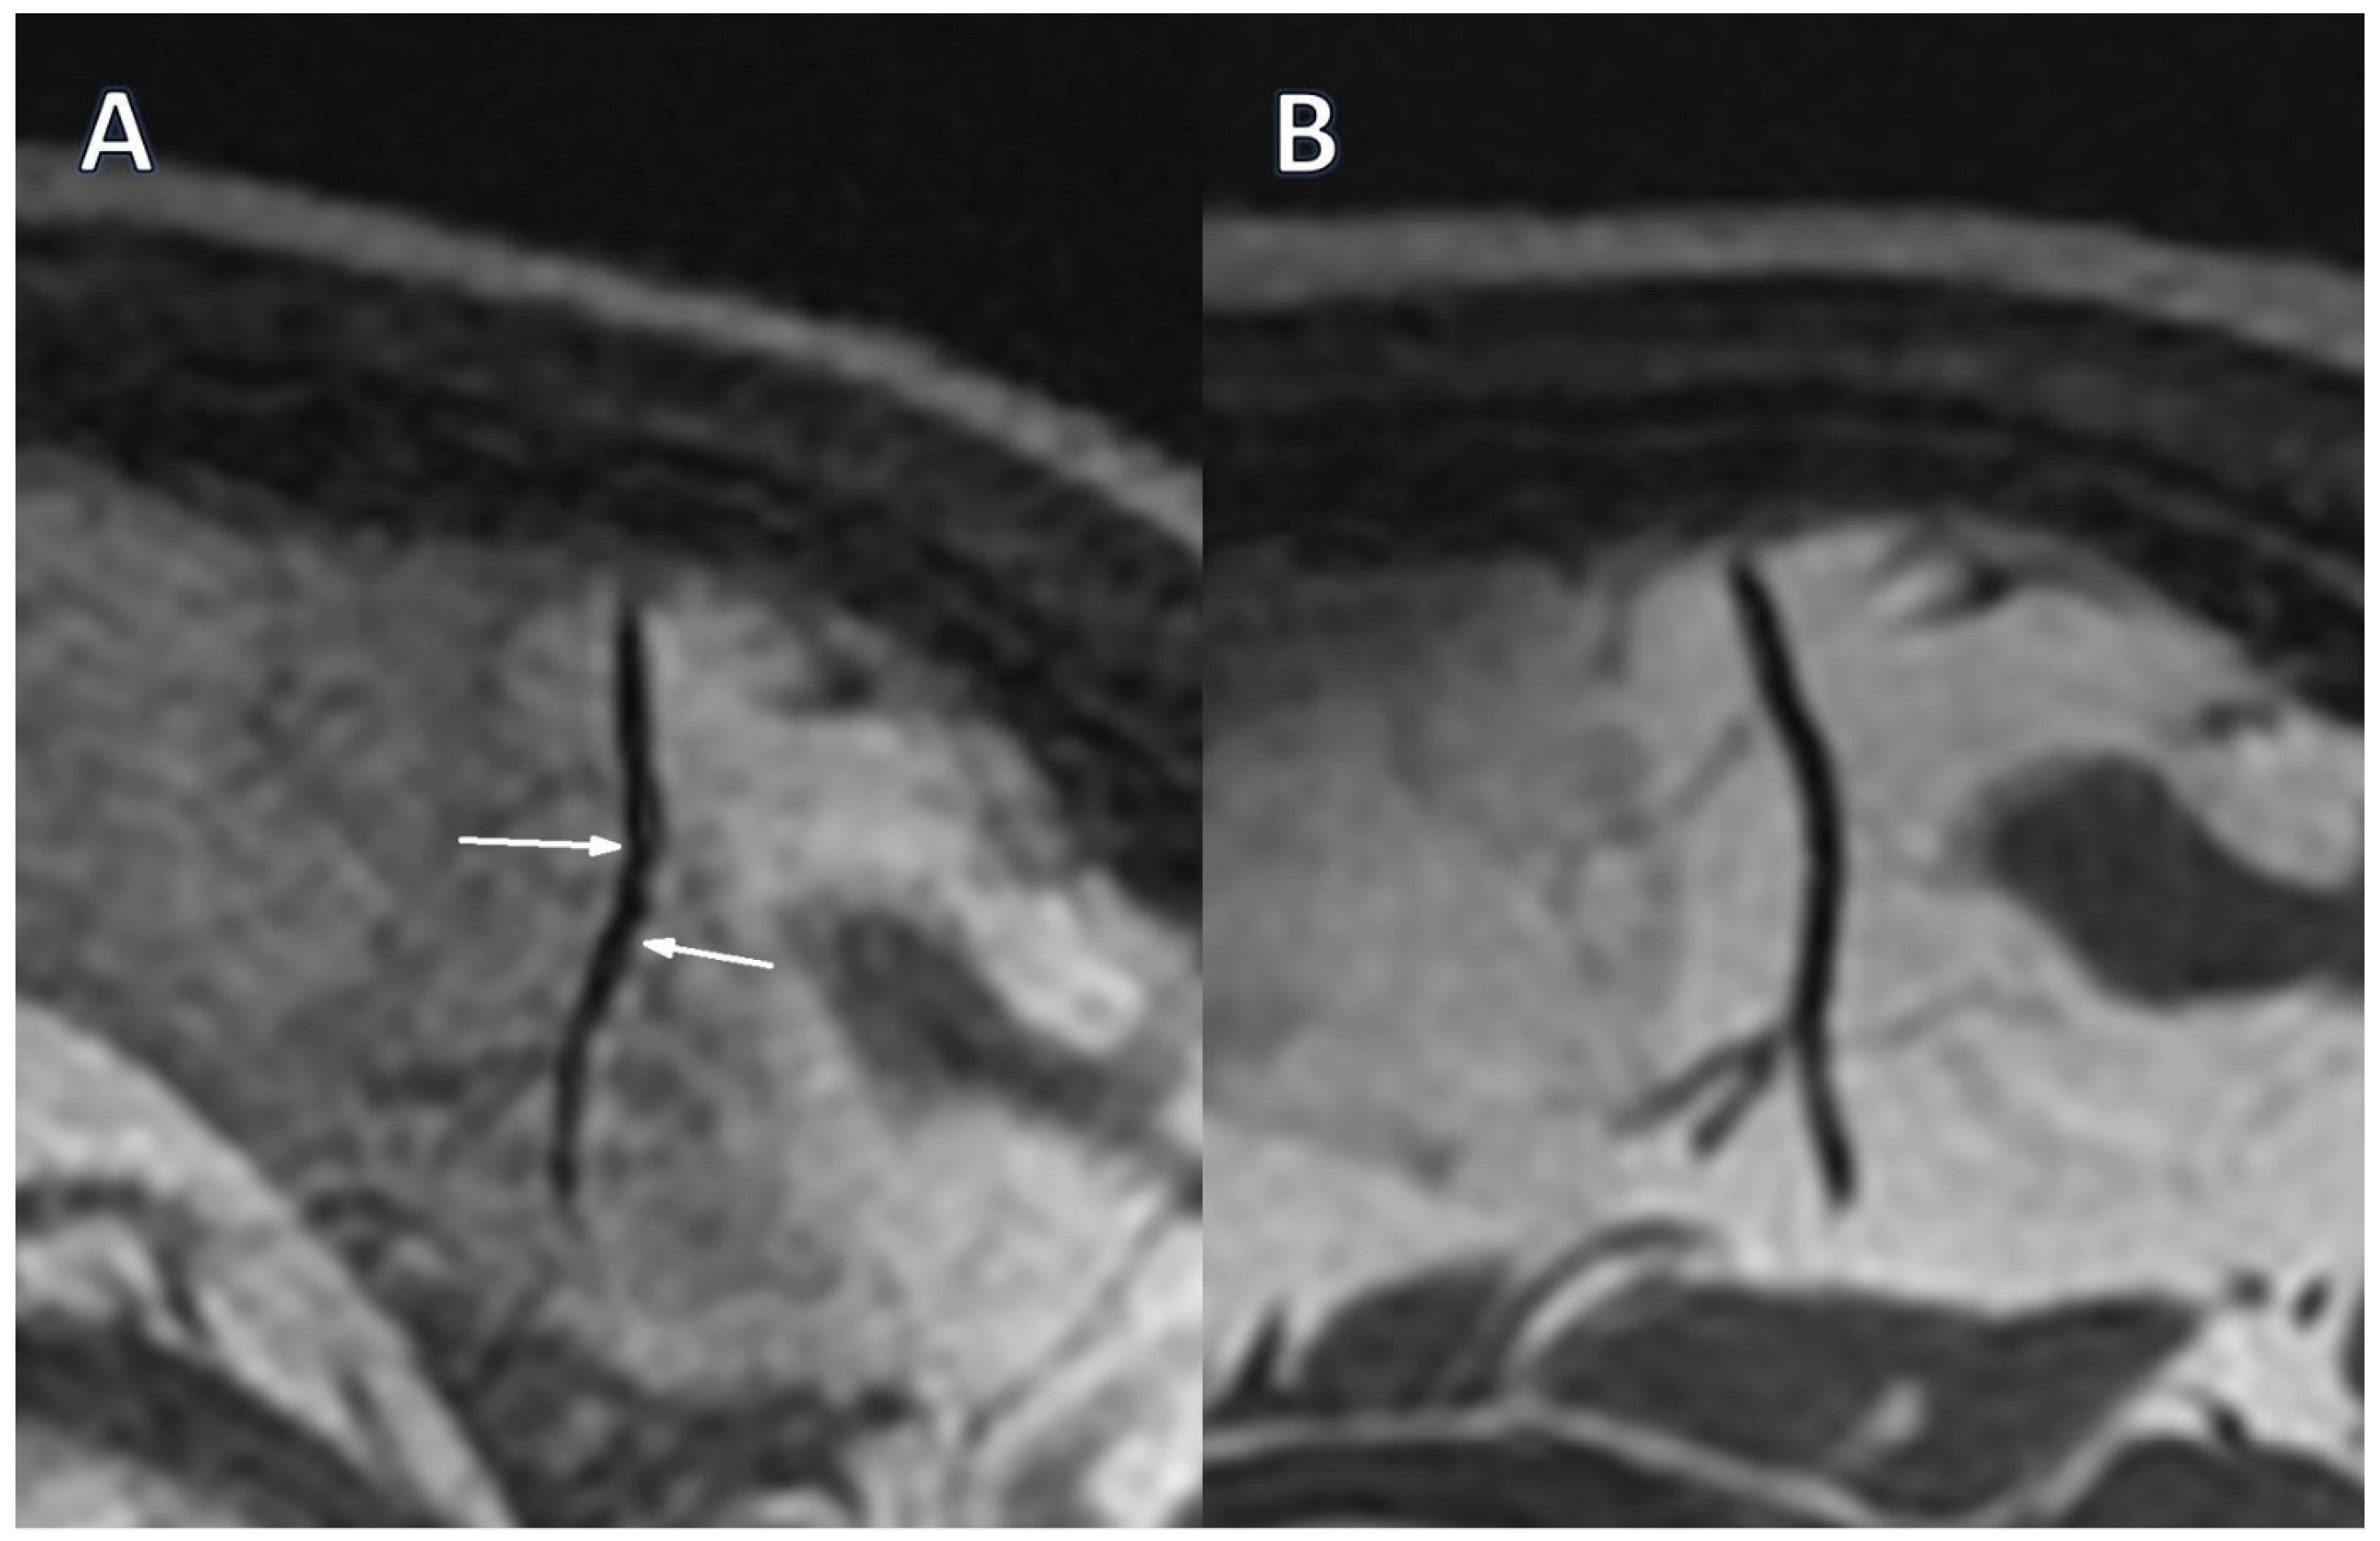

Only two segmental arterial narrowing in secondary vascular branches were investigated in Stage 0 TOF, which were absent in Stage 1 (Table 3). However, this change was not substantial. The occurrence of VAND in secondary as well as in tertiary vascular branches was initially detected in the BB sequence in 37.9% of patients, with their reduction to 17.2% (p = 0.031) and 10.3% (p = 0.008) in Stage 1, respectively (Figure 1A,B, Figure 2A,B).

Figure 2. The intracranial vessel in the sagittal plane in the BB STIR T2 sequence. (A)—Alternating narrowing and dilatation (white arrows) before treatment (Stage 0); (B)—Normalization of vessel lumen after treatment (Stage 1).